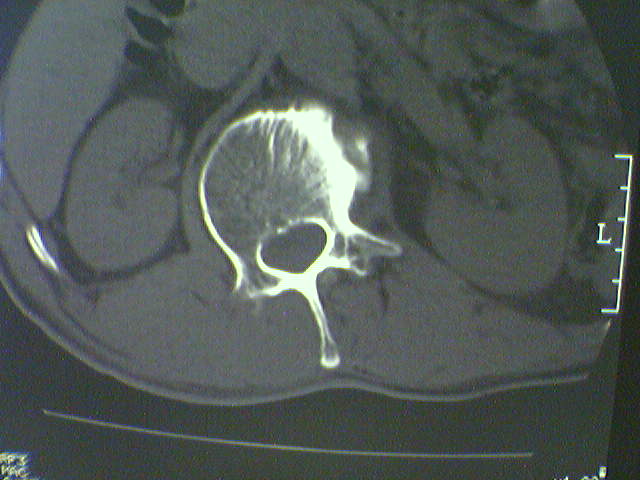

标题: CT15569:男,45岁.腰痛多年,平片腰椎明显侧弯, [打印本页]

标题: CT15569:男,45岁.腰痛多年,平片腰椎明显侧弯,

退行性骨增生软组织硬化;应有平片以除外椎体滑脱